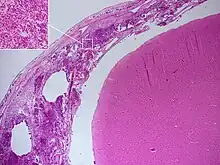

Postmortem

Meningitis can be diagnosed after death has occurred. The findings from a post mortem are usually a widespread inflammation of the pia mater and arachnoid layers of the meninges. Neutrophil granulocytes tend to have migrated to the cerebrospinal fluid and the base of the brain, along with cranial nerves and the spinal cord, may be surrounded with pus – as may the meningeal vessels.[52]